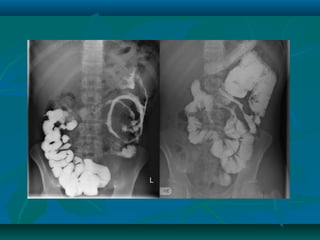

Radiology

Plain ABD. X-ray:

•Intestinal obstruction or displacement of

bowel loops by a mass.

Ultrasound:

•Thickened small bowel loops and

mesentery or abscess

Barium follow through:

•Asymmetrical alteration mucosal pattern

with narrowing or stricturing.

•Skip lesions

•Extent of the disease can be judge by air

distribution in the colon and the presence

of colonic dialatation

•Thickening of colonic wall and presence

of free fluid in abdominal cavity

•Fine mucosal granularity

•Mucosa become thickenned and

superficial ulcers are seen (collar-button

ulcers)

•Loss of haustration

Cont…..

CD

UC

Instant Barium enema

•Patchy sup. Ulceration to wide spread

deep (rose thorn ulcer)

•Cobble stone appearance and narrowing

•Superficial ulcers

•Shortened and narrowed colon in long

standing disease